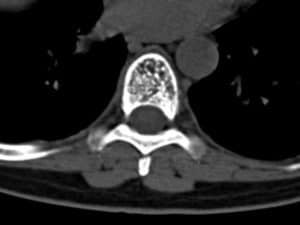

A vertebral hemangioma is type of benign spinal tumor. In adults, they are usually identified incidentally on CT or MRI.

Vertebral hemangiomas are usually slow growing. Radiological studies have described a growth rate of up to 3 mm over 10 years.

Less commonly, they can be aggressive. Still, symptoms are uncommon. When they do exist, symptoms can be localized pain or neurological.

Treatment is by decompressive surgery. Treatment for recurrence is sometimes offered with irradiation.